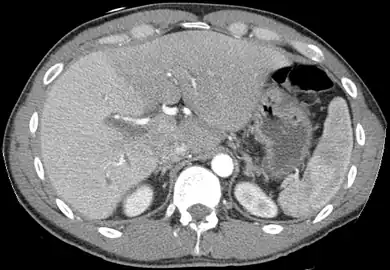

A CT scan in which the liver and portal vein are shown

With the recent advances of noninvasive imaging, living liver donors usually have to undergo imaging examinations for liver anatomy to decide if the anatomy is feasible for donation. The evaluation is usually performed by multidetector row computed tomography (MDCT) and magnetic resonance imaging (MRI). MDCT is good in vascular anatomy and volumetry. MRI is used for biliary tree anatomy. Donors with very unusual vascular anatomy, which makes them unsuitable for donation, could be screened out to avoid unnecessary operations.

MDCT image. Arterial anatomy contraindicated for liver donation

MDCT image. Portal venous anatomy contraindicated for liver donation

MDCT image. 3D image created by MDCT can clearly visualize the liver, measure the liver volume, and plan the dissection plane to facilitate the liver transplantation procedure.- Phase contrast CT image. Contrast is perfusing the right liver but not the left due to a left portal vein thrombus.